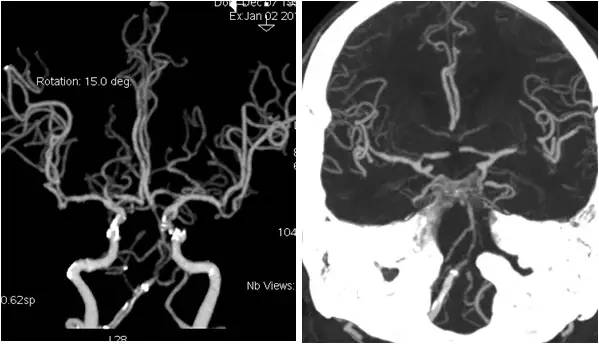

MRA:基底动脉中远段重度狭窄,右后交通动脉开放,左胚胎型大脑后动脉,双颈内动脉颅内段及双大脑中动脉多发轻-中度狭窄(图2)。

图2